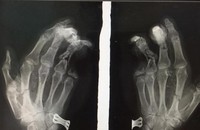

BS. Nguyễn Hoàng Quân - Khoa Phẫu thuật Chi trên và Y học thể thao, Bệnh viện Hữu nghị Việt Đức - cho hay: Ngay sau khi tiếp nhận bệnh nhi, các bác sĩ đã nhanh chóng thăm khám xác định bé bị tổn thương phức tạp dập nát bàn tay trái, cụt chấn thương ngón II, III, đứt gân gấp sâu ngón IV, trật hở khớp bàn ngón III. Các bác sĩ đã tiến hành cắt lọc, găm kim, nối gân, sửa mỏm cụt cho bệnh nhi.

![]() |

Bác sĩ kiểm tra phim chụp Xquang của bệnh nhi (Ảnh - BVCC) |

Sau 4 ngày phẫu thuật, vết thương của bé đã khô, ngón tay 3,4 hồng hào. Bé đang tiếp tục được theo dõi và điều trị tại Khoa Phẫu thuật Chi trên và Y học thể thao, Bệnh viện Hữu nghị Việt Đức.